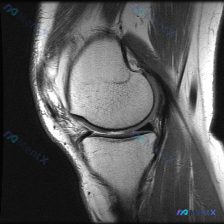

最近碰到一个有意思的病例,核心矛盾是「主诉考虑软骨异常,但影像学没看到明确病变」,整理出来和大家分享一下思路。 病例基本信息 核心问题:患者主诉提示膝关节存在软骨异常,仅提供单张膝关节MRI-T1序列矢状位影像,已完成影像读片分析。 影像读片结果 1. 骨性结构:股骨远端、胫骨近端、髌骨骨皮质完整,...

今天遇到一个有意思的读片问题:临床怀疑膝关节软骨异常,但提供的单张矢状位T1加权MRI读下来基本正常,整理一下分析思路和大家分享。 一、现有病例影像资料整理 这是一张膝关节矢状位T1加权MRI,图像质量清晰,信噪比良好,可见层面包含股骨远端外侧髁、胫骨近端、后交叉韧带、半月板前后角、髌韧带及Hoff...